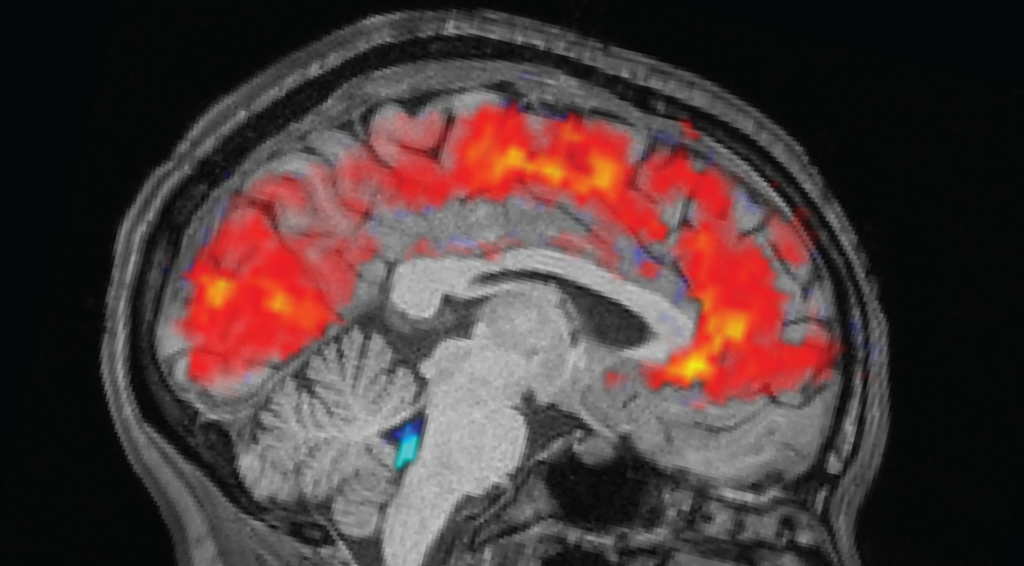

The rested individuals slept for 6.5 to 9 hours at home, while sleep-deprived individuals were kept awake all night in the laboratory. In the morning before each trial, the team strapped electroencephalogram (EEG) caps onto the participants to record their brain waves with electrodes. Simultaneously, the participants underwent functional MRI (fMRI) scans to reveal patterns in blood and CSF flow in the brain. Eye-trackers measured the participants’ pupil size.

The participants then completed tasks that flexed their visual and auditory attention; they pressed a button as soon as they saw an image or heard a noise. Additionally, the researchers gathered data on baseline brain activity by having the participants rest for 25 minutes without doing any tasks.

As expected, participants took longer to notice the stimuli when tired, and missed the cues more often than they did when they were well rested. But the team was surprised to see giant pulses of CSF in the exhausted individuals, alongside patterns of slow brain waves — both of which are normally observed in non-REM sleep.

Specifically, the patterns resembled that seen as a person shifts from stage N1 into N2, the first two of three stages of non-REM sleep that people experience each slumber. “This was something that previously we’d only seen on this scale during sleep,” Lewis said.